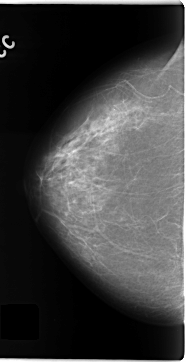

C_0135_1.LEFT_MLO

RIGHT_CC LINES 4704 PIXELS_PER_LINE 2408 BITS_PER_PIXEL 12 RESOLUTION 50 NON_OVERLAY

RIGHT_MLO LINES 4672 PIXELS_PER_LINE 2528 BITS_PER_PIXEL 12 RESOLUTION 50 NON_OVERLAY